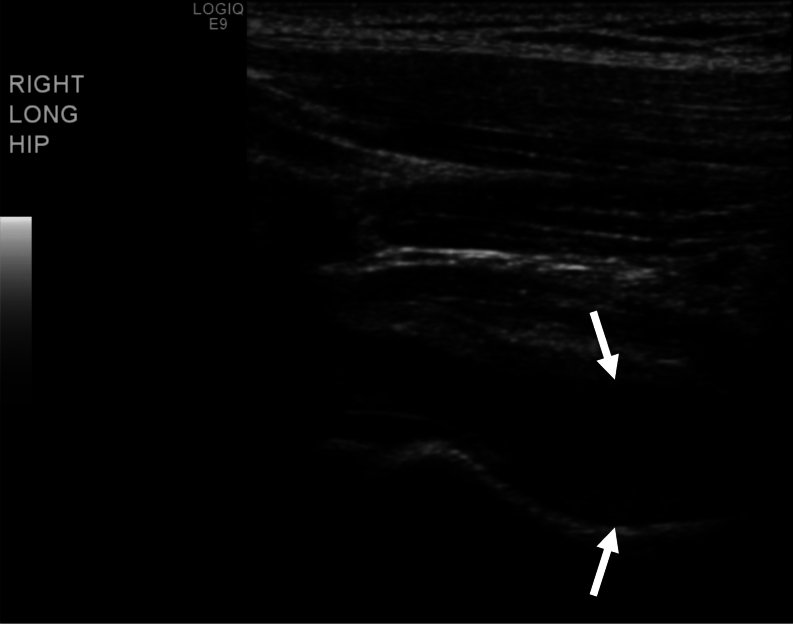

Summary: A 6.6-year-old female presented to endocrinology with precocious puberty for evaluation and management. Workup was initiated, and a diagnosis of central precocious puberty was confirmed. A decision was made to initiate pubertal blockade using gonadotropin-releasing hormone agonist (GnRHa) therapy with depot leuprolide acetate injections every 3 months. The patient received the first depot leuprolide acetate injection in the right ventrogluteal area. Six hours following the injection, the patient was reported to be inconsolable in pain, which was localized to the right hip site of the earlier injection and associated with a refusal to ambulate. The pain and discomfort continued to progress over the next 24 h despite an alternating regimen of Tylenol and ibuprofen prompting admission to the emergency department. Vital signs demonstrated a low-grade fever and elevated C-reactive protein. An ultrasound of the right hip demonstrated fluid accumulation within the joint. Over the next week, the patient was unable to walk independently and required assistance for activities of daily living. By 2 weeks after the injection, the pain began to remit, and the patient resumed activities of daily living. Following consultation with allergy, a decision was made to continue GnRHa suppressive therapy with an alternative analog (Triptodur). The patient tolerated subsequent treatment without reaction.

Learning points: Although gonadotropin-releasing hormone agonists (GnRHa) have a generally good safety profile, there is a history of both local and systemic hypersensitivity reactions associated with their use. Despite the long-acting formulation of depot leuprolide acetate, the systemic reaction in this case appears to be self-limited. Discontinuation of therapy or a change to an alternative formulation of GnRHa analog should be considered based on the need for therapy versus the potential risk of rechallenge.